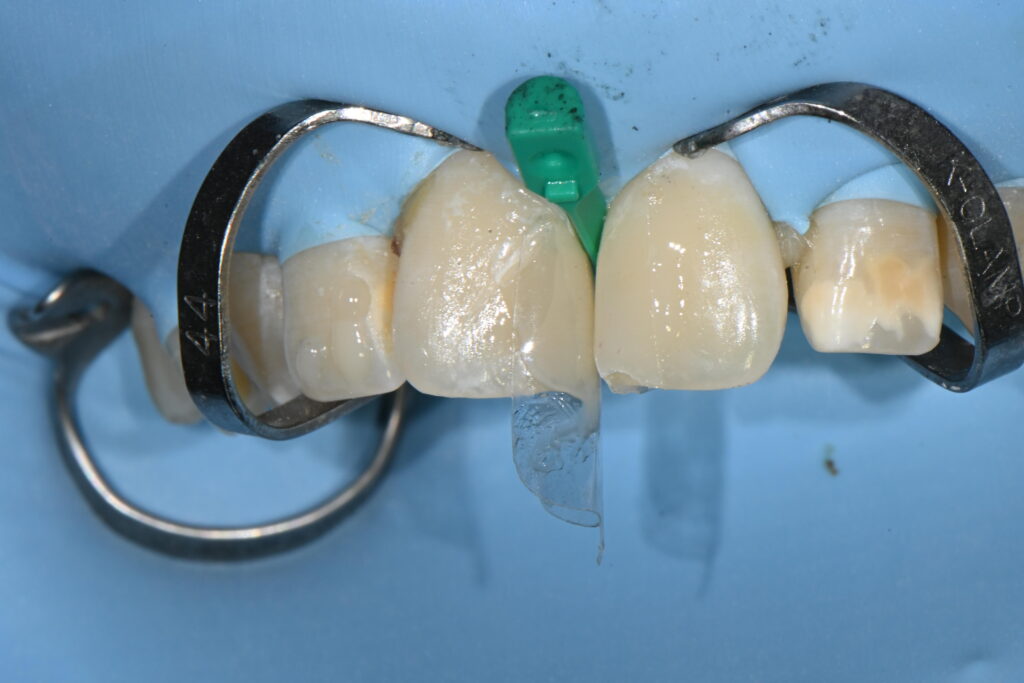

적절히 치아의 모양에 맞는 바이오클리어라는 재료를 이용하여

모양을 만들어야 합니다

본딩이후 바이오 클리어 시적 과정

여기서 모양과 색상이 결정되는 가장 중요한 포인트입니다

모양을 잘 만들어주어야 하는것이지요

이 과정 자체가 시간이 너무 많이 걸리기 때문에

원래 총4개의 치아를 치료하기로 했으나

정중앙 앞2개의 치아만 치료하기로 했습니다

양쪽이 동시에 레진이 충전완료 되었습니다

적절하게 치료가 진행이 되고 있는데요